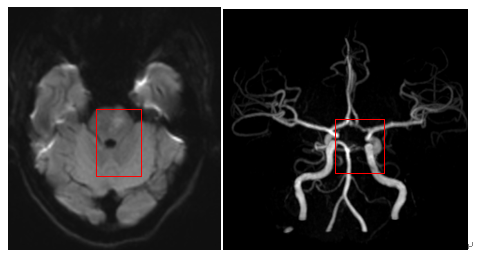

入院后患者神志转清,却突然出现言语不清、右侧肢体无力等症状——典型脑卒中表现。当晚值班医师立即联系放射科,完善头颅 MR +MRV 检查。检查结果提示头颅 MR:脑干左侧急性梗死。头颈部 CTA:基底动脉闭塞——这是致死致残率极高的危急重症,每延迟 1 分钟抢救,就有 190 万个神经细胞永久死亡。

手术在紧张有序地进行,术中发现患者左侧椎动脉夹层导致基底动脉闭塞,成功取栓并辅以抗凝治疗。术后第二天,患者言语不清,右侧肢体无力的症状就明显好转,双侧 Babinski 征转阴。

一周后复查头颅 MR+MRA 提示,闭塞基底动脉,夹层的椎动脉,均已开通。患者临床症状完全消失,没有留下任何后遗症!